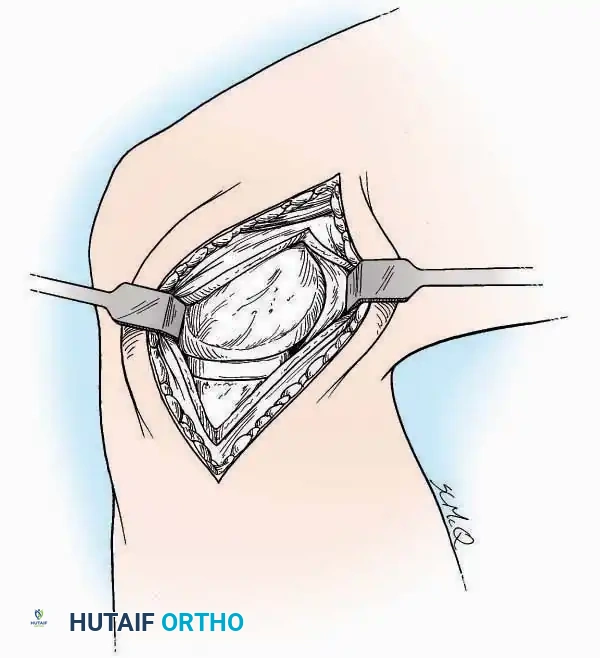

Kocher Approach (Curved L)

Indications: Complete excision of the calcaneus (calcanectomy) for malignant tumors or recalcitrant osteomyelitis.

Surgical Technique:

* Incision: Incise the skin over the medial border of the Achilles tendon, starting 7.5 cm proximal to the calcaneal tuberosity. Extend it distally to the inferoposterior aspect of the tuberosity, curve it transversely around the posterior heel, and continue distally along the lateral surface of the foot to the tuberosity of the fifth metatarsal.

* Deep Dissection: Divide the Achilles tendon directly at its insertion and carry the dissection down to the bone.

* Enucleation: To reach the superior surface, free all tissues beneath the severed Achilles tendon. The calcaneus can then be enucleated subperiosteally or extraperiosteally depending on the oncologic or infectious margins required.